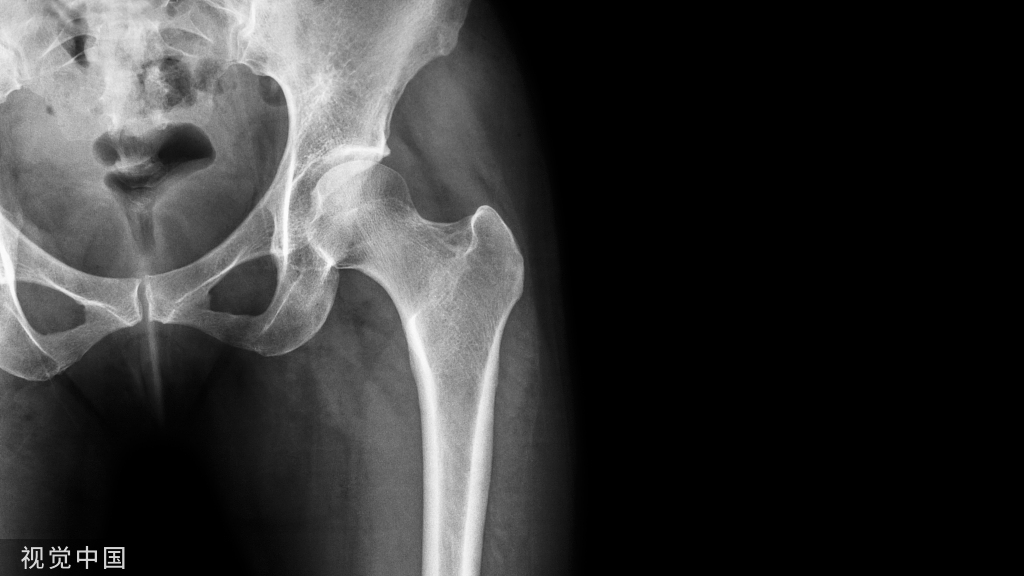

双动臼杯可以通过任何传统的手术入路进行置入。如图3所示手术入路,髋关节由后侧入路暴露。暴露髋部骨折部位并且切除股骨头。

图3 后方入路暴露髋关节